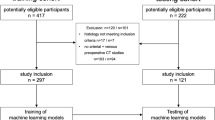

Publications between 2017 and 2021 on radiomic MVI prediction in HCC based on CT, MR, ultrasound, and PET/CT were included. The risk of bias was assessed using the prediction model risk of bias assessment tool (PROBAST). Methodological quality was assessed through the radiomics quality score (RQS). Fourteen studies classified as TRIPOD Type 2a or above were used for meta-analysis using random-effects model. Further analyses were performed to investigate the technical factors influencing the predictive performance of radiomics models.

Twenty-three studies including 4947 patients were included. The risk of bias was mainly related to analysis domain. The RQS reached an average of (37.7 ± 11.4)% with main methodological insufficiencies of scientific study design, external validation, and open science. The pooled areas under the receiver operating curve (AUC) were 0.85 (95% CI 0.82–0.89), 0.87 (95% CI 0.83–0.92), and 0.74 (95% CI 0.67–0.80), respectively, for CT, MR, and ultrasound radiomics models. The pooled AUC of ultrasound radiomics model was significantly lower than that of CT (p = 0.002) and MR (p < 0.001). Portal venous phase for CT and hepatobiliary phase for MR were superior to other imaging sequences for radiomic MVI prediction. Segmentation of both tumor and peritumor regions showed better performance than tumor region.